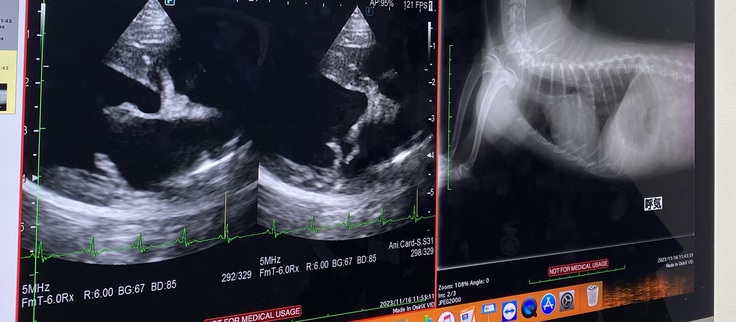

検査の結果 【僧帽弁閉鎖不全症】

ステージB2との事で3種類の投薬開始

ステージB2との事ですが

予断を許さない状態です。